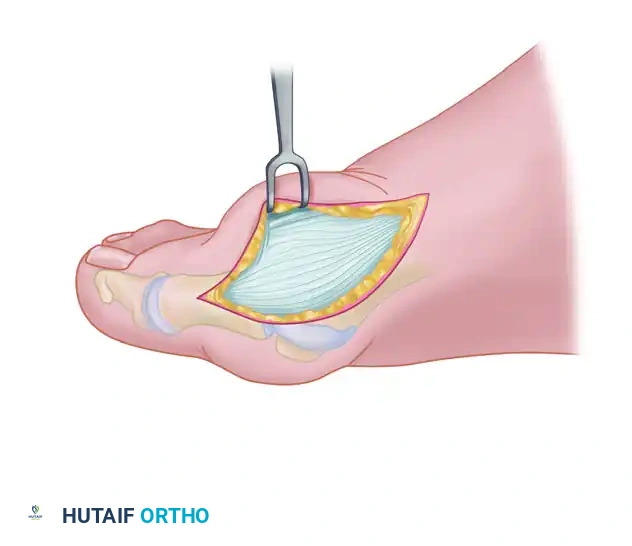

Medial Eminence Removal (Exostectomy)

The goal of the exostectomy is to remove the prominent medial bump without compromising the weight-bearing surface of the metatarsal head or the tibial sesamoid articulation.

- After inspecting the MTP joint for loose bodies or synovial hypertrophy, prepare for the exostectomy. Always consult the preoperative weight-bearing radiographs to determine the exact amount of medial eminence to be resected. Over-resection can lead to loss of tibial sesamoid support and subsequent hallux varus.

- First, score the proximal edge of the eminence with an osteotome where it meets the metatarsal shaft. This critical step prevents the osteotomy from propagating proximally and splitting the metatarsal shaft.

- Using a power saw (a 9-mm blade is preferred over a 4- to 5-mm blade for stability) or a sharp osteotome, begin the exostectomy distally at the parasagittal groove. Direct the cut medially toward the previously scored area on the metatarsal shaft.

- After the medial eminence has been removed, use a small rongeur to round off the sharp dorsal and plantar edges of the medial aspect of the metatarsal head.

- Conclude this stage by rasping the raw cancellous bone to a smooth contour. Apply bone wax to the raw bony surfaces of the metatarsal head to minimize postoperative osseous bleeding and hematoma formation.